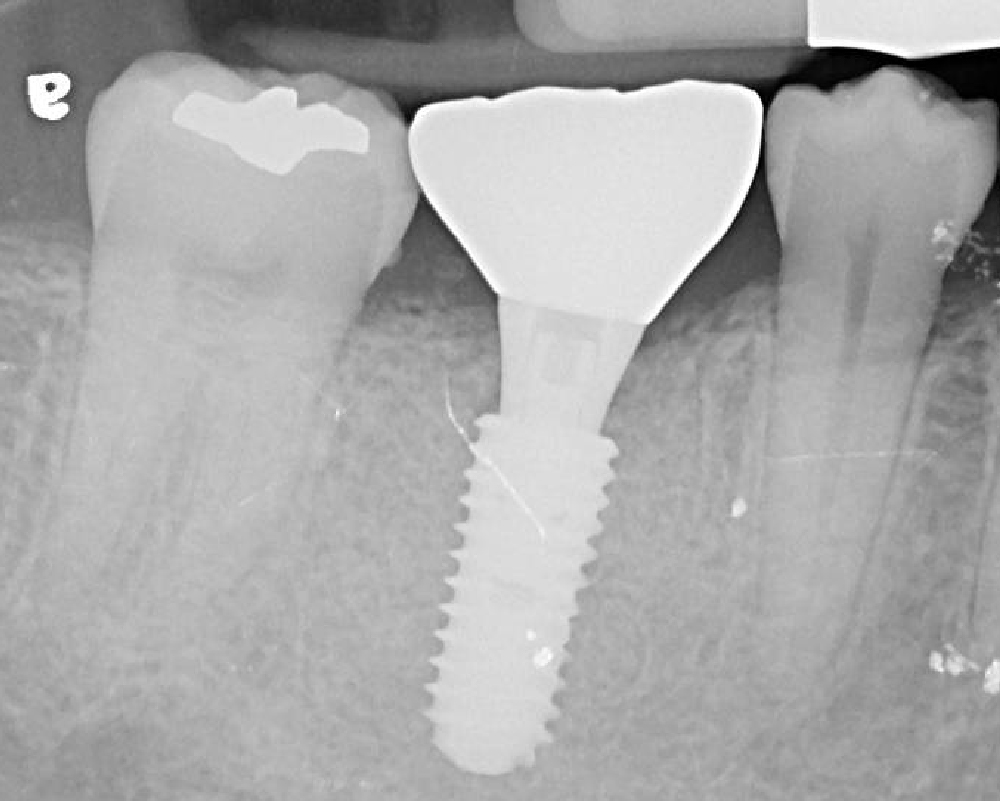

案例解析:L先生的右下第一大臼齒咬裂

治療前:牙齒疼痛疑似有牙根斷裂

治療後:單顆植牙恢復咬合